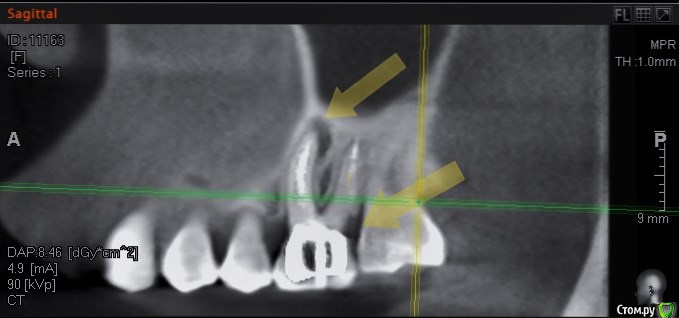

колесников Опубликовано 15 августа, 2016 Поделиться Опубликовано 15 августа, 2016 Здравствуйте, трещину седьмого зуба не увидел на кт, возможно в полости рта видно. На КТ он выглядит вполне нормально для попытки спасения.С шестым вот большой вопрос в сохранении, возможно нарушена целостность корня. Верхний шестой тоже обязательно лечить, вокруг корней тоже воспаление. Итого: то что видно на КТ. на трех зубах очаги воспаления. Трещин не видно ( их и не будет видно) Все три зуба можно попытаться вылечить, шансы 50/50. По моему всё очевидно. 37 трещина по бифуркации,тотальная резорбция межкорневой перегородки и ограниченно -вестибулярной пластинки. 36 перфорация медиального корня в верхней трети с очаговой деструкцией в области межкорневой перегородки. Итого: 37 удаляется без вариантов. 36 удаление можно отсрочить на несколько месяцев ,но шансы на восстановление у него призрачны (перспективы перелечивания с закрытием перфорации в устье канала сомнительны,плюс остаётся нерешаемый очаг деструкции в перегородке) 2 Ссылка на комментарий

DmitrySH Опубликовано 16 августа, 2016 Поделиться Опубликовано 16 августа, 2016 По моему всё очевидно. 37 трещина по бифуркации,тотальная резорбция межкорневой перегородки и ограниченно -вестибулярной пластинки. 36 перфорация медиального корня в верхней трети с очаговой деструкцией в области межкорневой перегородки. Итого: 37 удаляется без вариантов. Если это трещина, то очень странная. Коллега, все может быть, но по КТ( не самого лучшего качества) выносить приговор зубу.. я пас. 36 удаление можно отсрочить на несколько месяцев ,но шансы на восстановление у него призрачны (перспективы перелечивания с закрытием перфорации в устье канала сомнительны,плюс остаётся нерешаемый очаг деструкции в перегородке) Не хочу переводить тему во флуд, но опять все боятся процессов в фуркации. 1 Ссылка на комментарий

колесников Опубликовано 16 августа, 2016 Поделиться Опубликовано 16 августа, 2016 (изменено) Есть проблема и у верхней шестёрки. Деструкция на верхушке медиального щёчного корня. Это лечится. Есть карман пародонтальный между 26 и 27. Это лечится. Но есть и подозрение на кариес корня . Этот вопрос решится только после снятия коронки. Изменено 16 августа, 2016 пользователем колесников Ссылка на комментарий